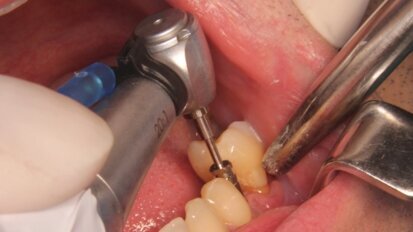

Zerwanie śruby mocującej przenośnik wszczepu stomatologicznego jako powikłanie śródzabiegowe

Rosnąca popularność rehabilitacji braków zębowych z wykorzystaniem wszczepów stomatologicznych może przynosić coraz większą liczbę ...